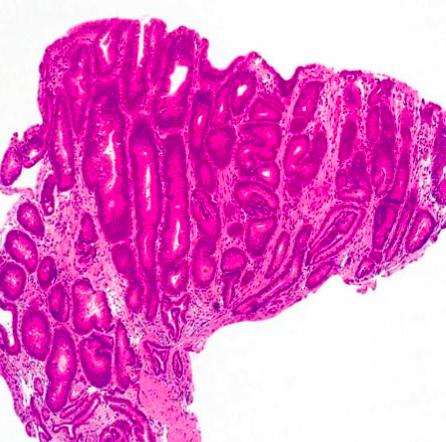

<p>What type of stomach polyp is this?</p>

<p><u>Hyperplastic polyp</u> caused by either:</p>

<ul>

<li><em>H. pylori</em>OR</li>

<li>Auto-immune gastritis</li>